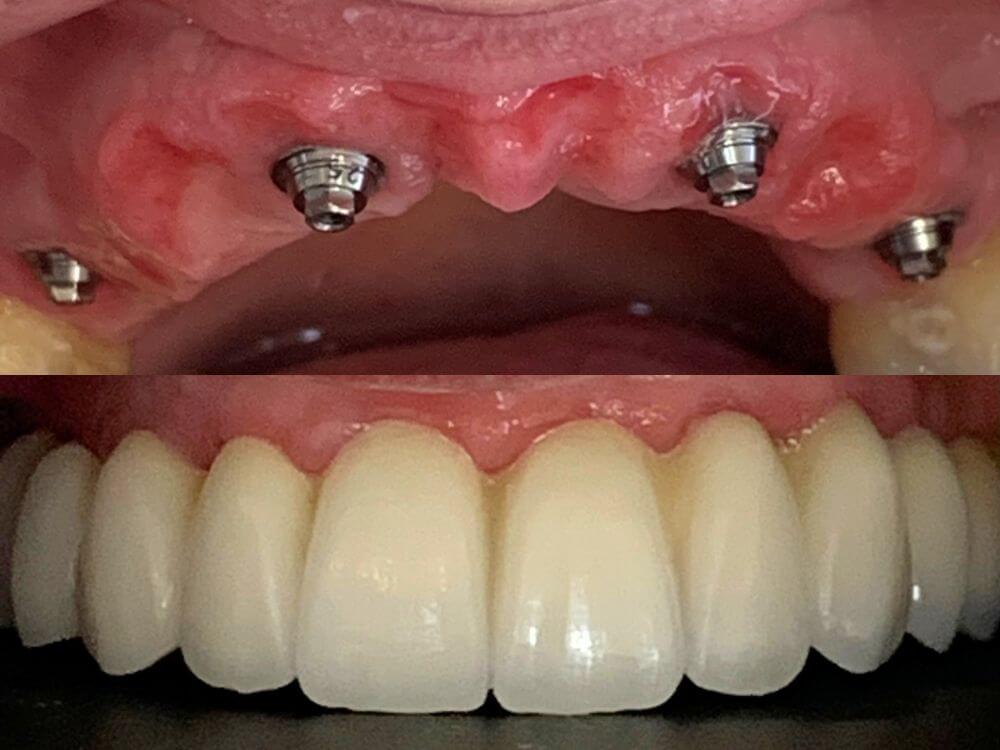

Com apenas 4 implantes é possível instalar uma prótese fixa com todos os dentes da arcada. Não necessita enxerto ósseo. Solução rápida e altamente eficaz.

Implantes e a prótese são instalados no mesmo dia. Resultados estéticos e funcionais rápidos. Em até 72 horas, seu sorriso é completamente reconstruído.

Uma prótese total fixa sobre implantes para quem perdeu todos os dentes de uma arcada. Recupera a força na mastigação e elimina desconforto ao falar e mastigar.